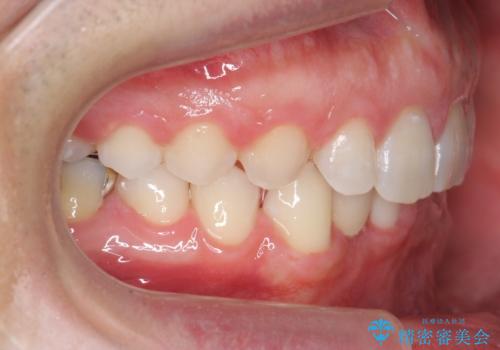

上はインビザラインで目立たないように前歯を下げ、下は難しいため、ワイヤー矯正で咬み込んでいる下の歯を沈める処置を初め行いました。最終的には上下ともインビザライン矯正で仕上げました。

下の前歯が生まれつき1本少なかったため、その部分には最終的にインプラントを入れ、下の歯が下がりすぎないようにかつ上の前歯にしっかり咬むように仕上げました。

今回は、時間はかかりましたが矯正治療で隙間を閉じ、天然の歯を保存することができました。セラミックで無理に一時的にかぶせるとその後大変な人生になるのが予想されます。

難ケースのため、患者様とともに根気強く治療に取り組んだ結果、しっかり治療することができました。